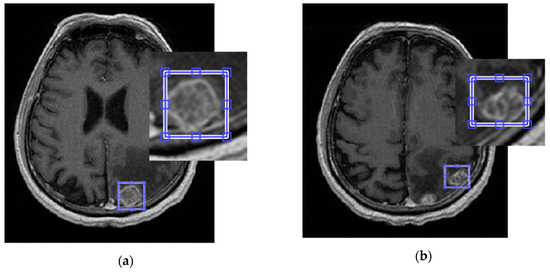

In this preliminary step, a user specifies a volume of interest (VOI) by drawing a rectangular region on one slice of the input volume and selecting first and last slices in such a way that the entire pathological area is bounded within the specified parallelepiped (see Figure 1).

Figure 1. (a,b) show two different source slices of T1c MR scans with the corresponding Volume slice perimeter bounding Brain metastases (BM) areas.